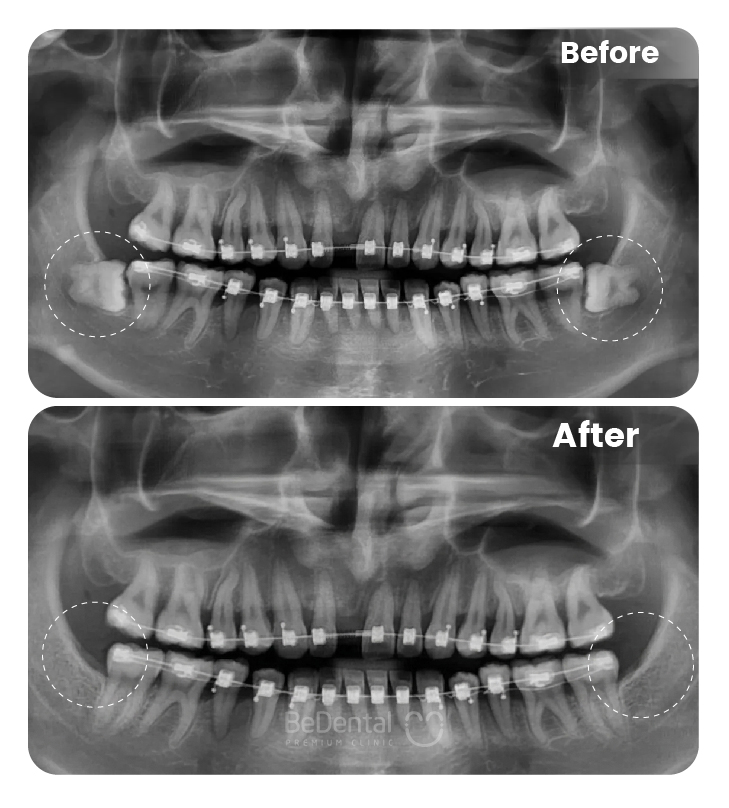

Trước khi điều trị, bác sĩ sẽ tiến hành thăm khám tổng quát, chụp X-quang, CT Cone Beam hoặc scan răng 3D để đánh giá chính xác vị trí răng, hướng mọc, mật độ xương và mối tương quan khớp cắn. Dựa trên các dữ liệu này, bác sĩ xây dựng phác đồ chỉnh nha cá nhân hóa, lựa chọn loại khí cụ phù hợp như mắc cài kim loại, mắc cài sứ hoặc khay niềng trong suốt.

Lực chỉnh nha được kiểm soát chặt chẽ, giúp răng di chuyển từ từ, sinh lý và an toàn từ vị trí mọc trên nướu về đúng cung hàm. Quá trình này không chỉ cải thiện thẩm mỹ mà còn giúp cân chỉnh khớp cắn, phân bổ lực nhai hợp lý, hạn chế nguy cơ mòn răng, đau hàm và rối loạn khớp thái dương – hàm.